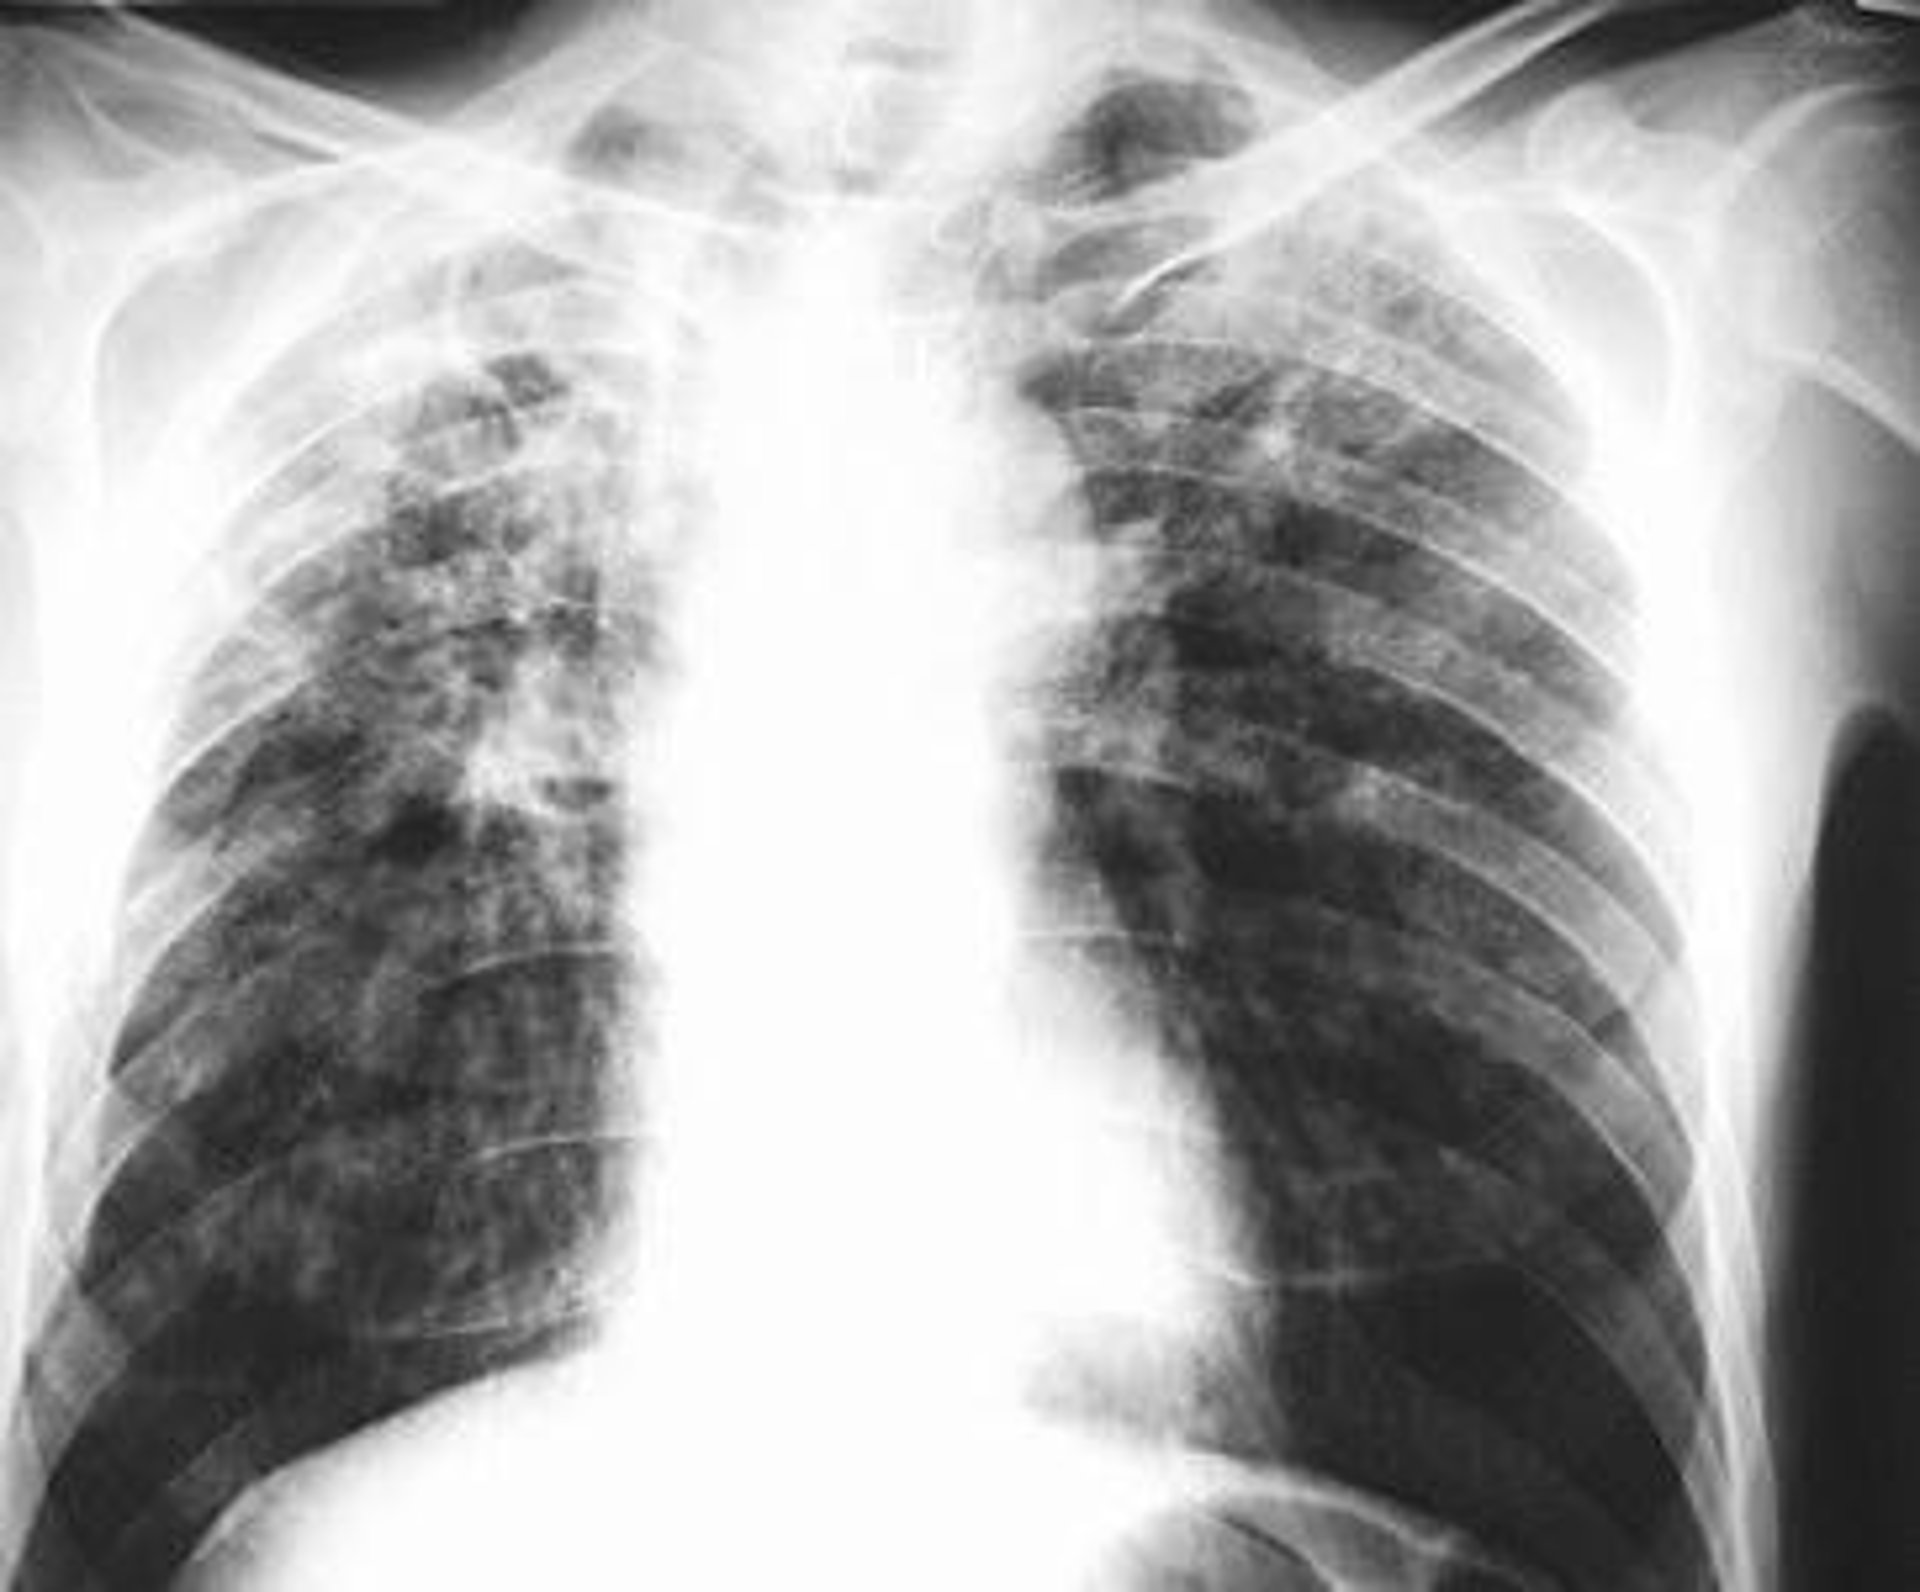

Fibras de colágeno pulmonar evitan la tuberculosis

La tuberculosis es una enfermedad infecciosa provocada por la entrada en el organismo de una bacteria del género 'mycobacterium', que normalmente se instala en los pulmones. Los síntomas de la enfermedad, que es muy frecuente que no se desarrolle o tarde muchos años en hacerlo, causan tos seca de más de semanas de evolución con fiebre, y ocasiona lesiones en los lóbulos pulmonares superiores, e incluso meningitis.

Ello causa constantes lesiones que no son destacables con las radiografías del tórax, el método diagnóstico que actualmente se utiliza para saber si una persona que ha dado positivo en la prueba de la tuberculina está desarrollando la enfermedad o no.